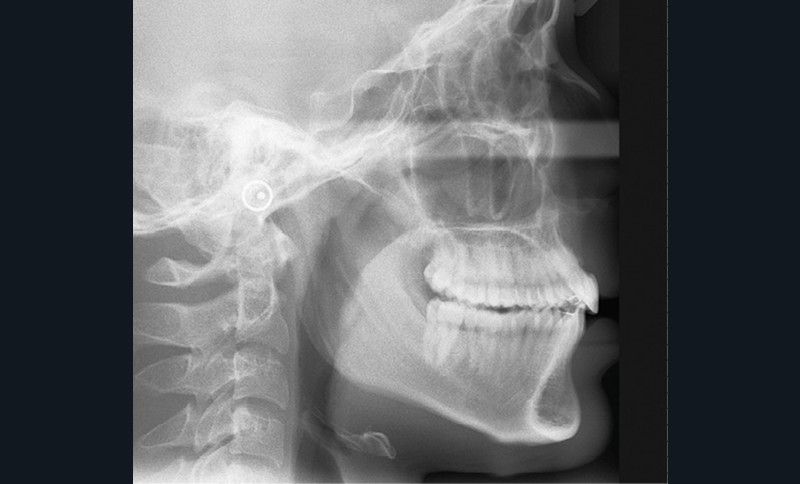

Une fois la croissance alvéolaire terminée, le patient est réadressé à son chirurgien-dentiste pour définir précisément, à l’aide d’une prévisualisation informatique (Digital Smile Design), quelle position dentaire et gingivale est recherchée pour les quatre dents antérieures (fig. 4 a,b) [4]. Le torque et le tip sont particulièrement importants à corriger dans cette phase de reprise de traitement (de quelques mois) car la position des collets et la conservation tissulaire en dépendent fortement.

Les restaurations composites transitoires réalisées au cours du premier traitement cherchant à restaurer l’esthétique de 12 et 22 masquent l’asymétrie de correction des axes radiculaires. La lecture des informations du deuxième et du troisième ordre est ainsi faussée par l’anatomie coronaire perturbée. Une individualisation par plicature est donc nécessaire pour s’approcher au mieux de la prévisualisation, avec pour seuls guides les axes radiculaires radiologiques et la position des collets souhaités (fig. 4a,b).

Plusieurs difficultés ont été rencontrées durant le traitement. L’impact psychologique des extractions d’incisives centrales a été lourd pour le patient, dont la promesse d’un sourire harmonisé a permis de surmonter cette épreuve. Ensuite, la gestion de la transposition était délicate. Il a fallu également accepter un rendu esthétique perfectible jusqu’à la fin de la croissance. La gestion de la dysharmonie dento-parodontale au niveau des incisives latérales et des canines était essentielle ; une correction parodontale et orthodontique, en jouant sur les informations de deuxième et troisième ordres, a permis une transition esthétique optimisée. L’outil de prévisualisation Digital Smile Design s’est en ce sens avéré très utile pour définir les impératifs propres à la prothèse (fig. 4a,b). Des frais pour la parodontie et la prothèse se sont enfin ajoutés aux dépenses orthodontiques (deux phases de traitement). Le rendu esthétique est satisfaisant en fin de traitement, avec une harmonisation du sourire et du profil (fig. 5 et 6). Les extractions n’ont pas appauvri le sourire. La qualité des réalisations prothétiques, l’environnement parodontal remanié et l’occlusion de fin de traitement font espérer un bon devenir dans le temps.